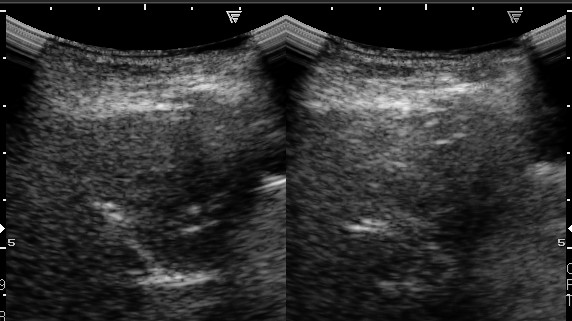

上顎洞超音波検査←妊娠中の方、小児

超音波検査は、小さいお子さんにも繰り返し行うことができ、妊娠中の方でも行える安全な検査です。しかし、上顎洞以外の副鼻腔については診断できません。レントゲンは、篩骨洞や前頭洞についてもある程度分かりますが、CTほど詳しい正確なところまでは分かりません。また、蝶形骨洞については、レントゲンでは全く分からず、CTが必要です。

- 副鼻腔炎を超音波検査で診断できるのですか?

超音波で診断できるのは副鼻腔のうち上顎洞だけですが、幼小児の副鼻腔炎はまず上顎洞に炎症を起こしますので、超音波検査で診断できます。また大人でも成人の急性副鼻腔炎の多くは上顎洞に炎症を起こします。レントゲン検査も1回撮るだけなら、飛行機で太平洋を往復して空から浴びる放射能より少ないぐらいですが、小児や妊娠している方はもちろん、普通でも必要最小限にとどめたいものです。

幼小児の副鼻腔炎と大人の急性副鼻腔炎は、主として上顎洞に起きますので、超音波検査で十分診断できます。年長児や大人の慢性副鼻腔炎では、レントゲンが必要な場合もありますが、それも正確な診断には不十分です。正確で詳細な診断には、CTが必要です。